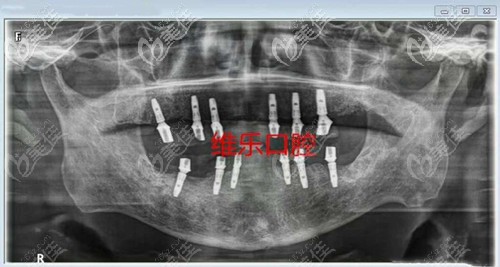

喏,牙齿种植后医生拍片就是这样的

从拍片可以看出我医生这个牙齿种植体的位置还是稳固的,而且爷爷的牙龈也好了挺多的。